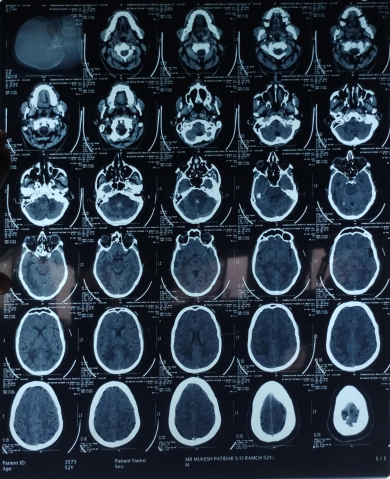

The patient’s routine blood investigations were normal. Serology for HIV, hepatitis B, C, and syphilis was negative. His MRI brain showed a parenchymal bleed in right temporo occipital regions with intra-ventricular leakage of blood and tiny petechial haemorrhage in brain parenchyma bilateral. extensive signal changes in cerebellar hemisphere, bilateral gangliothalamocapsular region, pons, midbrain and deep white matter of both cerebral hemisphere? Microangiopathy? CADASIL.

Early-onset dementia (onset before age 65) is a thought-provoking ailment with many possible causes, including early-onset familial Alzheimer’s disease, frontotemporal lobar degeneration, Parkinson’s dementia, Lewy body dementia, disorders of amino acid and organic acid metabolism, leukodystrophies, lysosomal storage diseases, disorders of metal metabolism, and mitochondrial diseases [6]. In our patient, the history, physical examination, laboratory investigations, and neuroimaging were not suggestive of these causes and prompted the search for a rare etiology. The most common MRI finding associated with CADASIL is basal ganglia and white matter hyperintensities in T2-weighted sequences that start as punctate or nodular foci and then often become confluent, extensive, and usually symmetrical, mainly in the periventricular region, anterior temporal pole, external capsule, the centrum semiovale, and frontal and parietal areas. In our patient, diagnosis was made mainly from MRI findings as seen in fig. 1, 2.

Fig. 2: Extensive hyperintensity on T2W/FLAIR sequence is seen in bilateral thalamus and basal ganglia, both cerebellar hemisphere, mid brain, pons and in deep white matter of both cerebral hemispheres